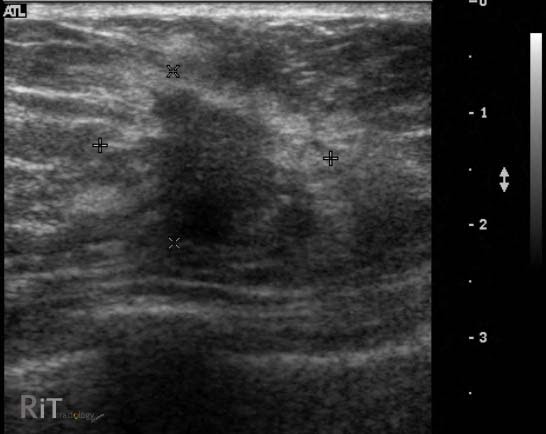

Cuando se sospecha la presencia de cáncer hepático, el Ultrasonido Hepatobiliar se convierte en una herramienta clave en la evaluación de posibles anomalías en el hígado. Este examen no invasivo permite a los profesionales de la salud obtener imágenes detalladas de la estructura hepática, identificando masas, cambios en la textura y otras irregularidades que podrían indicar la presencia de células cancerosas.

El Ultrasonido Hepatobiliar no solo ayuda a identificar la presencia de masas en el hígado, sino que también contribuye a diferenciar entre lesiones benignas y malignas. Esta capacidad para distinguir entre tumores cancerosos y no cancerosos es crucial para determinar el curso adecuado de tratamiento y ofrecer pronósticos precisos a los pacientes.

Además de la detección inicial, el Ultrasonido Hepatobiliar se utiliza para evaluar la extensión del cáncer hepático. Esta información es esencial para planificar intervenciones quirúrgicas, terapias de radiación o tratamientos farmacológicos. La capacidad de este procedimiento para proporcionar una visión detallada del estado del hígado guía a los profesionales en la toma de decisiones informadas.